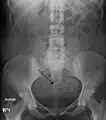

Multiple uterine leiomyoma

Multiple uterine leiomyoma with calcification

Fibroids are monoclonal tumors and approximately 40–50% show karyotypically detectable chromosomal abnormalities. When multiple fibroids are present they frequently have unrelated genetic defects. Specific mutations of the MED12 protein have been noted in 70 percent of fibroids.[29]